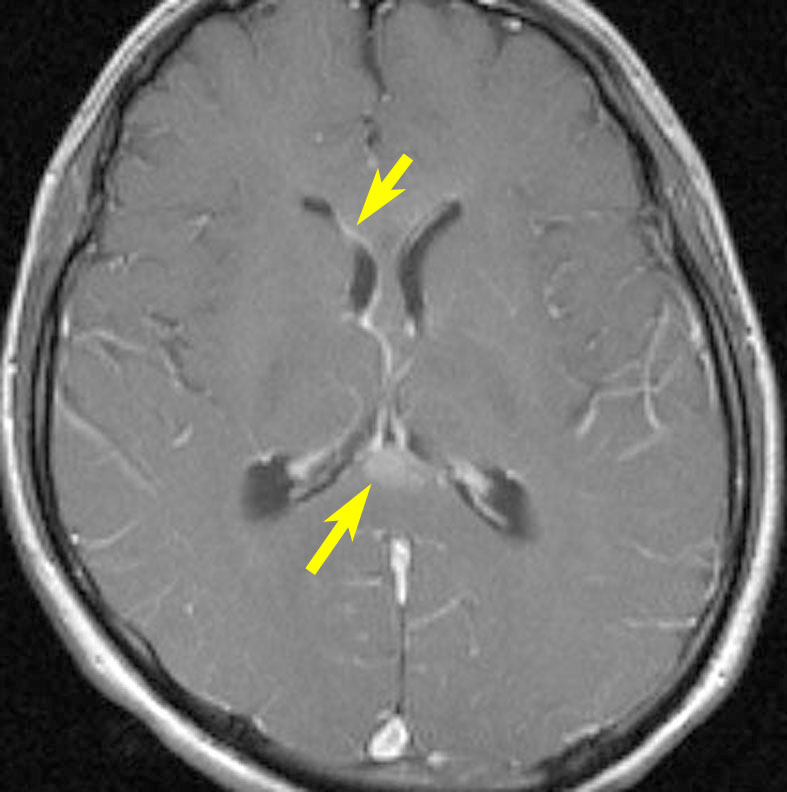

20歳くらいから尿崩症があり,2年後に汎下垂体機能低下症と軽度の認知機能低下を生じました。脳室壁と松果体,神経下垂体にジャーミノーマが広がっているのですが,脊髄背面と脳幹部の周囲にも腫瘍結節が見られました。脳室上衣以外の部位に腫瘍があるので,播種を疑いました。ジャーミノーマの播種というのは実際にはとても珍しくてなかなかみないものです。HCGは軽度の上昇,鼻孔から下垂体部分を生検して病理確定診断して,化学療法と脳脊髄照射 25.2Gy をしました。腫瘍は1コース目の化学療法でほとんど消失したので,他の組織型の悪性混合性胚細胞腫瘍ではないと考えられます。

3年後に脳室壁に再発しました。脳梁と脳弓の機能低下があり認知機能低下は高度でした。松果体と神経下垂体には再発はありません。